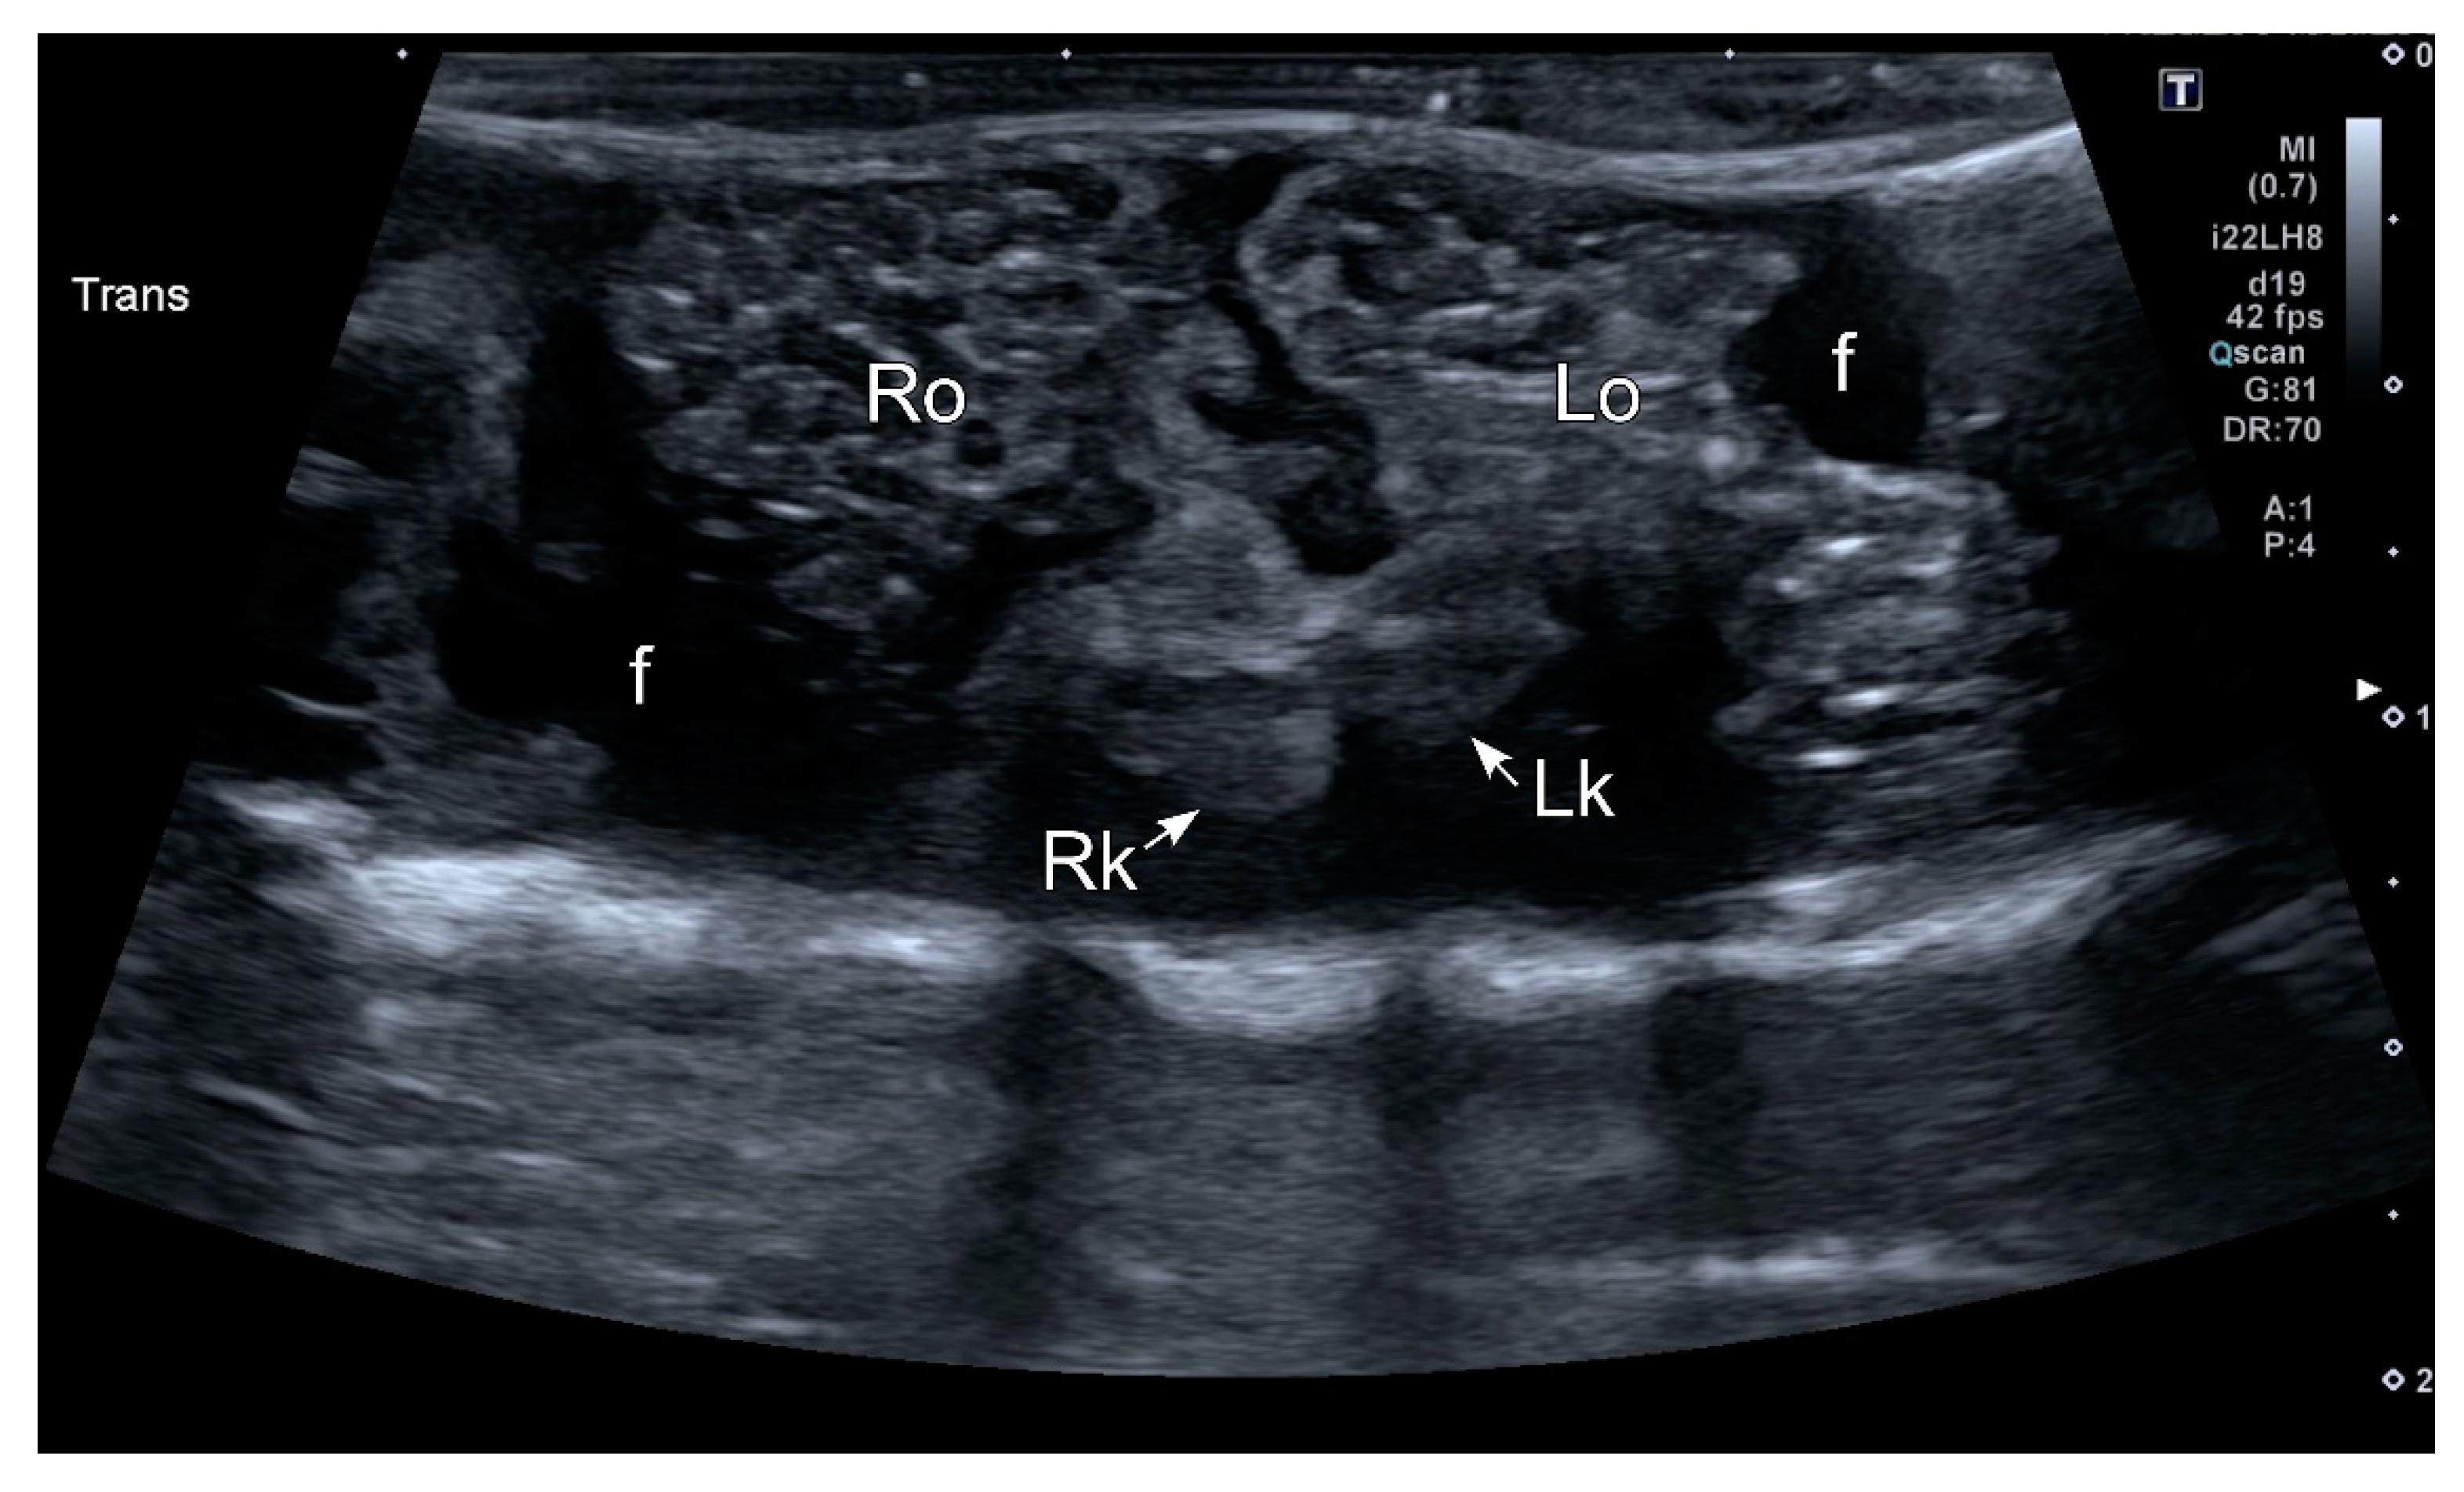

Figure 6. HR-US image of a female Kaloula pulchra obtained in the transverse plane using a ventral acoustic window. The image was taken just after oviposition. Both ovaries (right ovary: Ro; left ovary: Lo) appeared as hyperechoic structures with multiple hypoechoic foci which represent follicles. The kidneys are also visible (right kidney: Rk; left kidney: Lk). This animal had free fluid (f), which is considered normal in amphibians. The fluid around the ovaries improves its margin definition. |